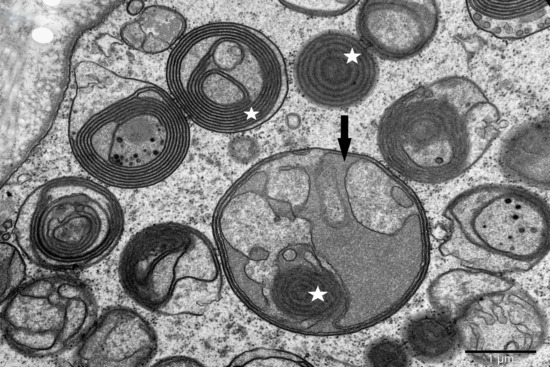

Atypical Phenotypes of Mitochondrial Cristae Architecture in Selected Human Aging Striated Muscles—Transmission Electron Microscope Studies

The diversity of mitochondria ultrastructure in human aging striated muscles is presented in relation to the complexity and variability of the cristae architecture and in relation to the environment of mitochondrial occurrence in the muscle fiber on the example of the orbicularis oculi. [...] Read more.

The diversity of mitochondria ultrastructure in human aging striated muscles is presented in relation to the complexity and variability of the cristae architecture and in relation to the environment of mitochondrial occurrence in the muscle fiber on the example of the orbicularis oculi. Ultrastructure analysis of mitochondria in muscles was performed using a transmission electron microscope. The studies revealed the presence of mitochondria of various sizes and unexpected shapes, and also modifications of the cristae architecture which included the occurrence of different configurations of membranes. In some mitochondria, instead of cristae, crystalline inclusion bodies and granules resembling calcium deposits were found. The range of diversity of the studied morphotypes of mitochondria exceeds the algorithms for the morphology of these organelles presented in the literature to date. This diversity of mitochondria should probably be viewed as a manifestation of evolution from the classical cristae architecture to a wide range of forms of mitochondria corresponding to the current environmental conditions of the muscle fiber. Full article